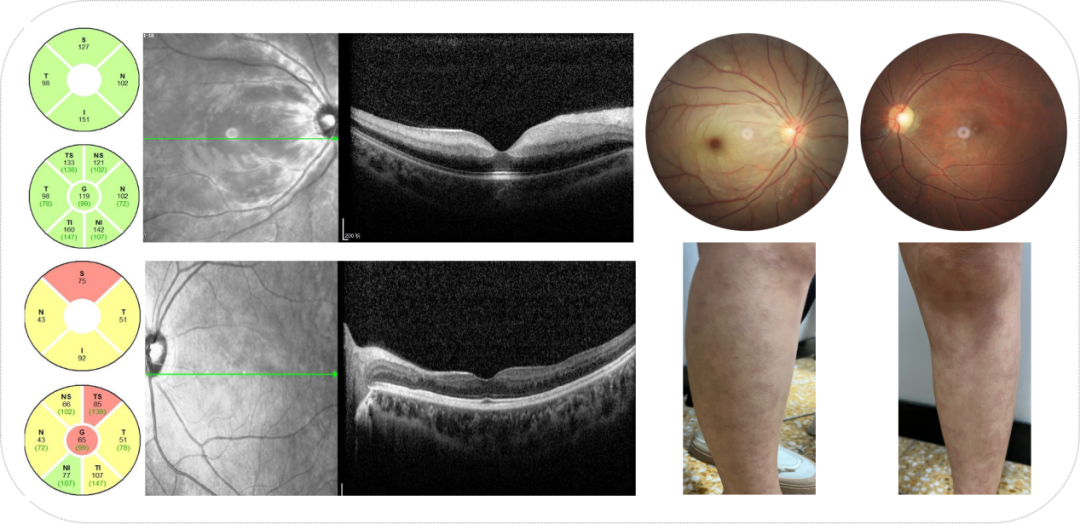

图片

图1.眼底像示右眼后极部视网膜水肿,黄斑区樱桃红斑,左眼后极部神经纤维束缺失。OCT示右眼视网膜内层组织水肿高反射,左眼视网膜部分内层萎缩变薄。双腿网格青斑样皮疹改变。